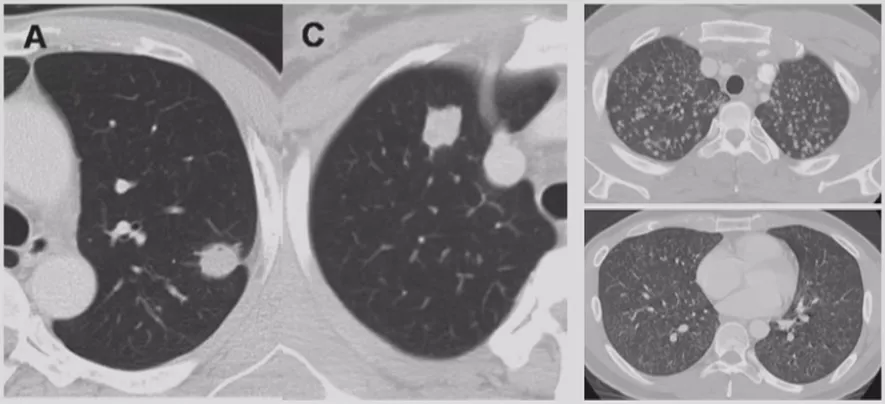

在临床上经常手术切除后发现是AAH,关于AAH的病人是否需要手术还存在很大的争议,有的认为不需要手术,观察就可以。那么我们在术前怎么评判是否为AAH?其实具有一定特征。一般来说,多位于肺外周,多<5mm,圆形或类圆形,边界清楚,多发更常见,绝大部分是均匀的纯磨玻璃影,里边没有实性成分。组织学检查AAH呈轻度到中度非典型立方柱状上皮细胞沿肺泡和呼吸性细支气管上皮增殖,无浸润,这样在临床上诊断AAH应该没有问题。但是,如下图所示,这个病人是多灶性病变,现在多灶性结节有所增多,会给临床的处理上带来一定压力。

多灶性COP

多灶性机化性肺炎也可以表现为胸膜下或支气管周围的磨玻璃密度片影伴实变,支气管或细支气管周围边界不清的磨玻璃密度小结节,大的结节和肿块,反Halo征。因此,大家在做肺结节鉴别诊断的时候一定要考虑到该疾病。

BOOP

双肺多发的磨玻璃影或斑片实变影,沿支气管血管束分布或位于胸膜下,在一个或多个结节内可见到支气管充气征,有时可见反晕征。临床上要是碰到多发性肺结节超过五个的问题倒不大,要是只有两、三个还是需要警惕的。